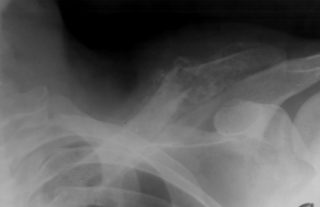

Переломы ключицы

Симптомы перелома сложно спутать с чем-то другим, ведь появляются они преимущественно после травм, о которых пациент помнит: удары, толчки, падения на выпрямленные руки или локти. Боль при переломах очень сильная, отечная, появляются синяки, кость может сменить привычное положение.

Вывихи и смещения

Вывих плечевого конца ключицы сопровождается острой болью

Грудинный конец ключицы, которым она крепится к клетке, может произойти из-за травм и падений, а также после ударов. Встречается патология редко и сопровождается такими симптомами:

- сильным отеком;

- выпячиванием ключицы или западанием;

- болью и покраснением.

Другой конец, акромиальный, имеет несколько связок, которыми крепится к лопаткам. Если они рвутся, пациент испытывает острую боль, возможность повернуть плечом резко ограничивается.